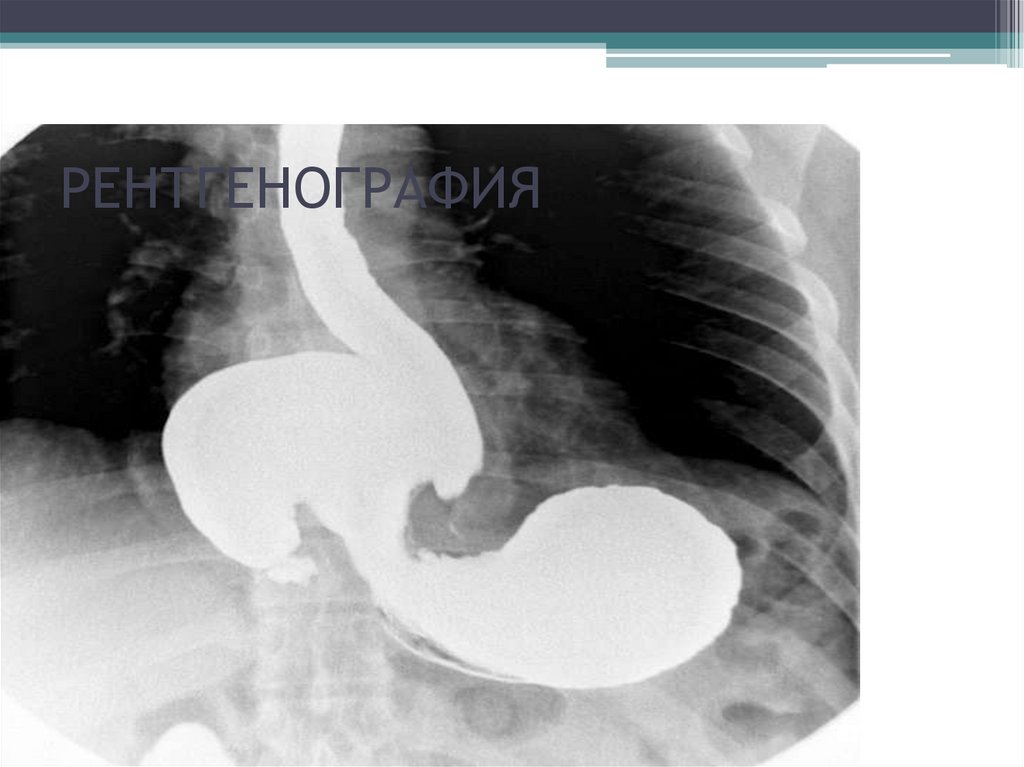

РЕНТГЕНОГРАФИЯ